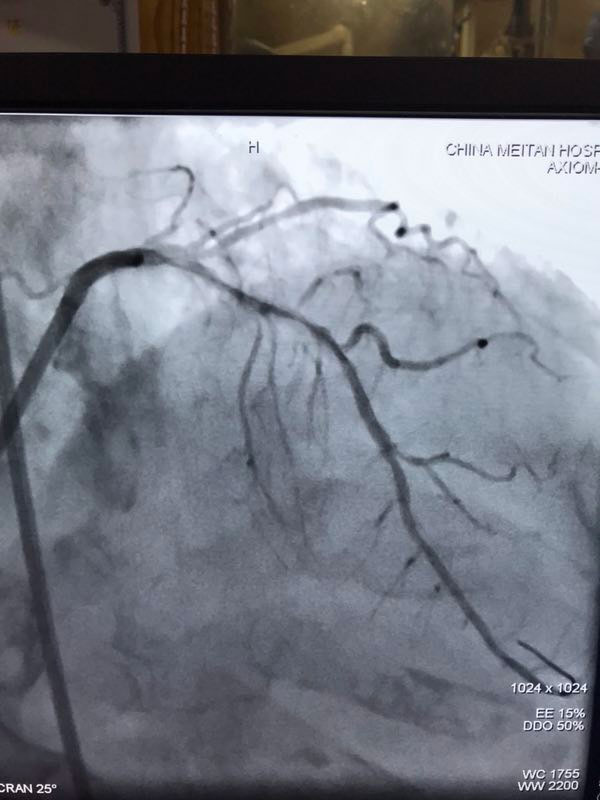

据了解,三位患者都是因严重心绞痛和非ST心梗入院,最高年龄88岁,另两名也有70多岁,是普通PCI难以治疗的危重患者。其中两名已辗转多家医院,均未得到有效救治。患者转入我院后,我院心内科在吴迪主任的带领下,经过周密的准备和科学评估,在血管内超声和临时起搏的辅助指引下,圆满完成了三台旋磨加PCI手术,术后IVUS显示治疗部位支架充分覆盖贴壁,彻底解决了三位患者的病痛,改善了长期预后。

据吴迪主任介绍,冠脉钙化病变和慢性闭塞病变一直是冠心病介入治疗的两大难题,特别是占20%比例的钙化病变,极大的难度风险及高并发症低成功率对心脏介入医生而言是巨大的壁垒和挑战。冠脉旋磨技术作为国家临床二类新技术,就是针对复杂严重钙化病变,通过特制的金刚石探头,在导丝指引氮气加压推进下送入冠脉,借助每秒高达17万转的高速旋转将钙化部位磨平断开,然后借助切割球囊分解斑块,为最终顺利植入支架创造条件。